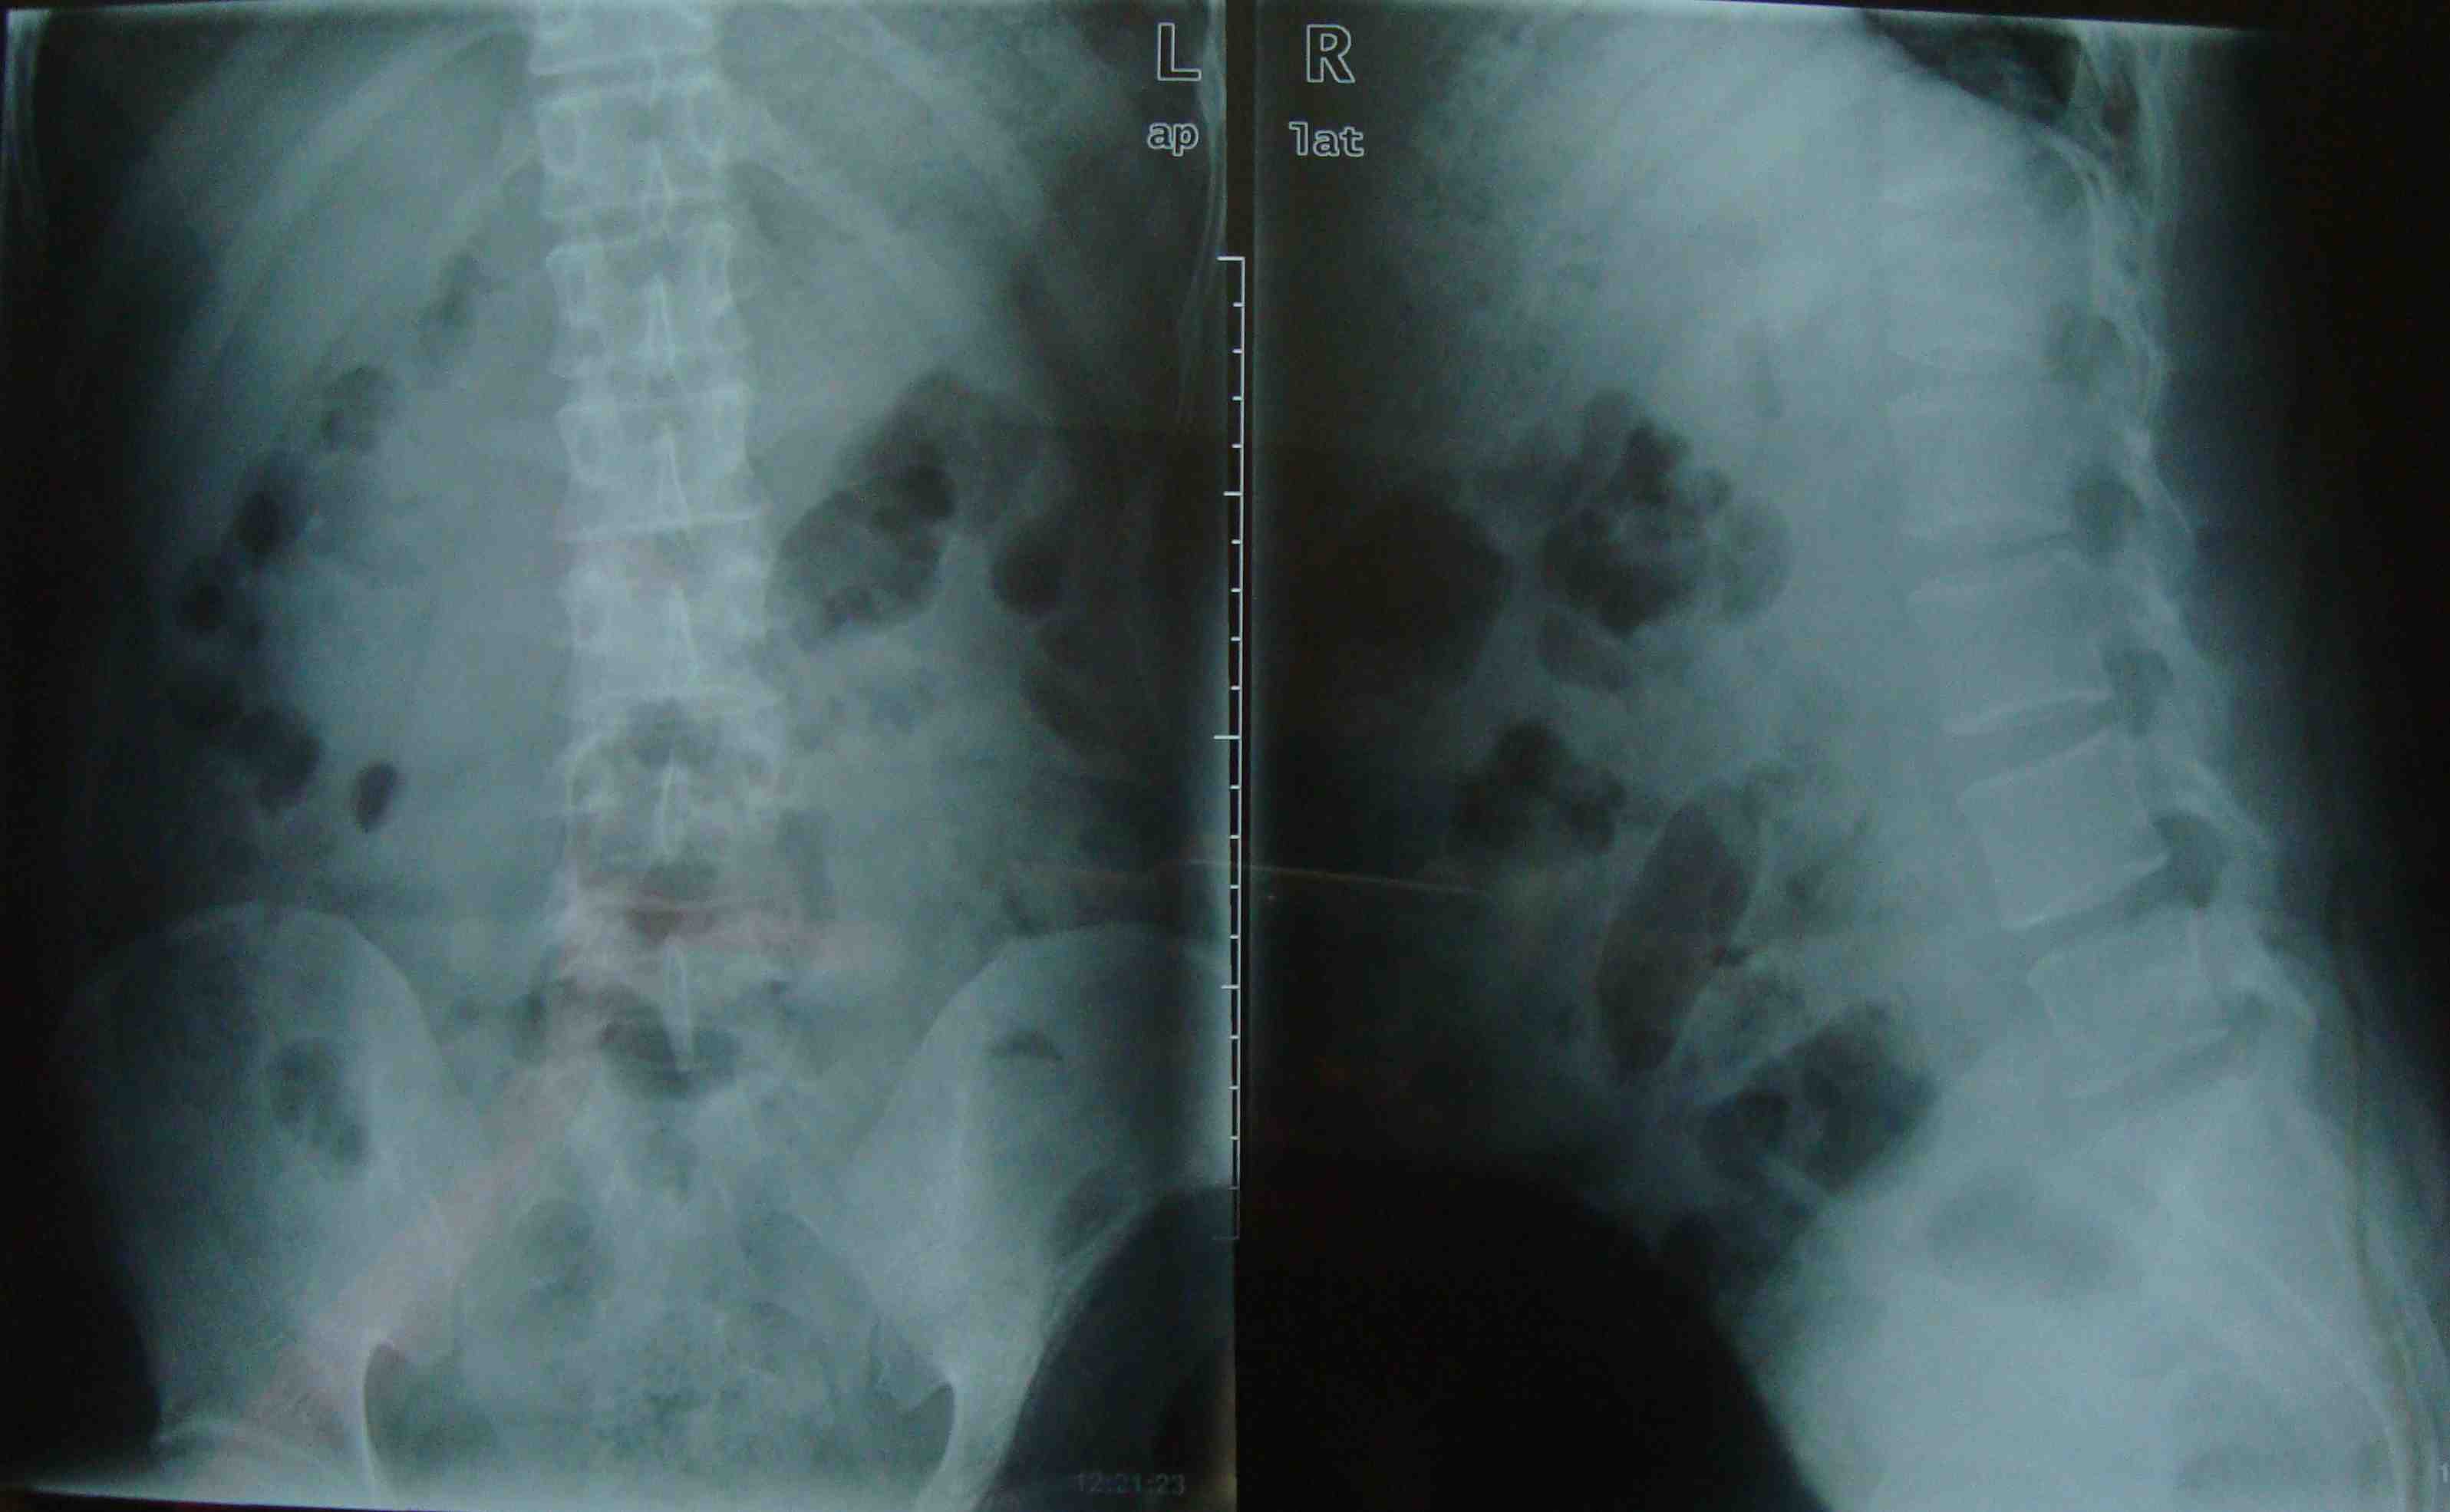

老年人胸腰椎退化改变x线图像腰背部疼痛表现为脊柱椎间隙丢失和脊柱